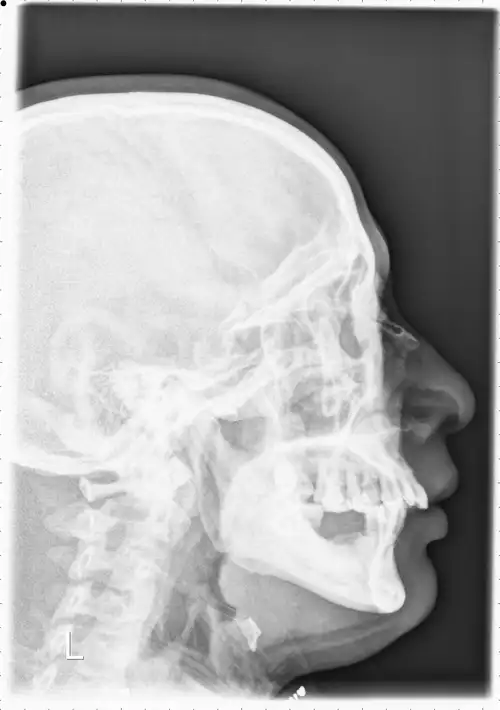

术前头颅ct显示,鼻假体弯曲,鼻骨内推术后,可见骨折